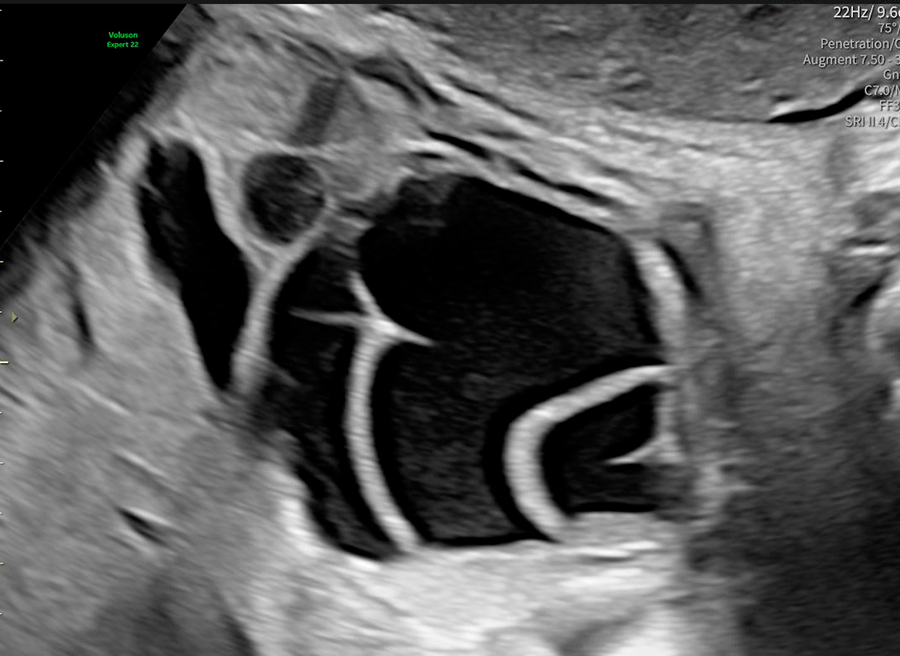

La ecografía ginecológica es un estudio por imágenes no invasivo que permite evaluar de forma precisa el útero, los ovarios y el sistema reproductor femenino. Es una herramienta fundamental para la detección temprana de alteraciones ginecológicas, el seguimiento de tratamientos y los controles preventivos.

En OBGYN Perú, realizamos ecografías ginecológicas con equipos de alta resolución, garantizando resultados confiables y una atención médica especializada.